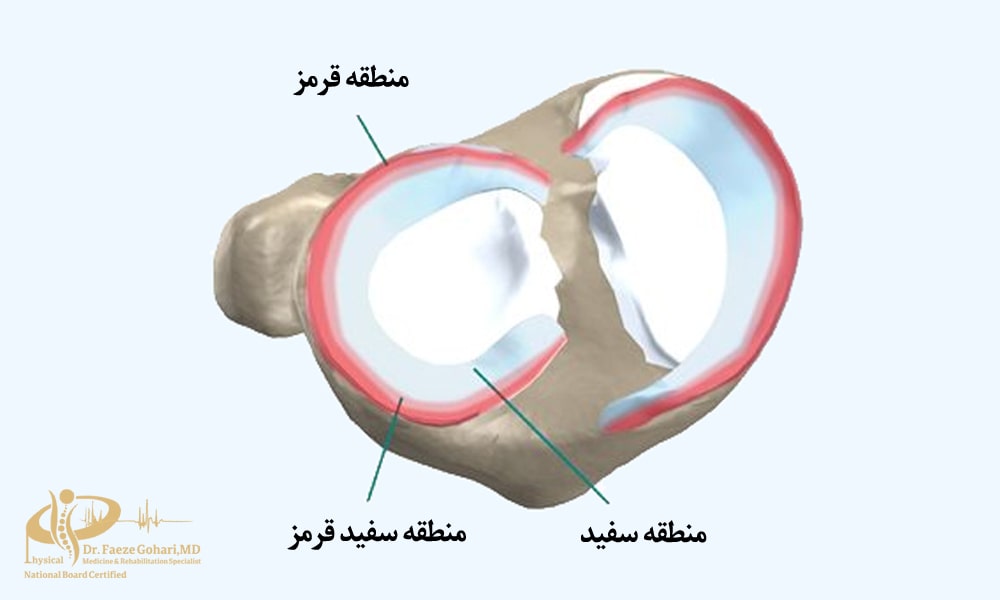

پیآرپی (پلاسمای غنی از پلاکت) میتواند به ترمیم ساختاری مینیسک کمک کند، اما این اثر به نوع و شدت پارگی بستگی دارد. در پارگیهای خفیف تا متوسط، بهویژه در نواحی با خونرسانی خوب (منطقه قرمز – قرمز یا قرمز – سفید)، فاکتورهای رشد آزادشده توسط پیآرپی میتوانند بازسازی بافت را تحریک کرده و به ترمیم ساختاری کمک کنند.

بااینحال، در پارگیهای شدید یا نواحی بدون خونرسانی (منطقه سفید – سفید)، توانایی پیآرپی برای ترمیم ساختاری محدود است و شواهد علمی بیشتر بر کاهش درد و بهبود عملکرد متمرکز هستند تا ترمیم کامل ساختاری. اثربخشی بلندمدت در ترمیم ساختاری نیز هنوز به تحقیقات بیشتری نیاز دارد. (منبع).